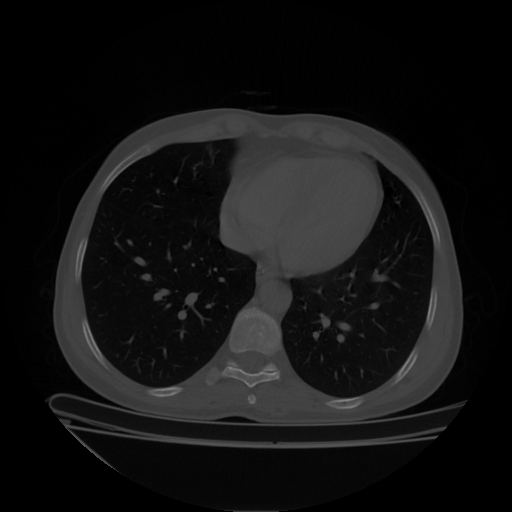

Reconstructed NATIVE CT scan (cycle consistency)

Full window (WL 1023.5, WW 4095 β†’ Low βˆ’1024, High +3071)

Lung window (WL -600, WW 1500 β†’ Low βˆ’1350, High +150)

Mediastinum window (WL 40, WW 400 β†’ Low βˆ’160, High +240)